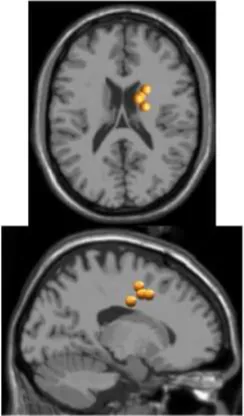

As expected the average treadmill belt velocity was more variable during active treadmill walking, regardless of command speed (Figure 3A). Average pelvis velocity in the sagittal plane was similar for the slow and fast walking commands, indicating the participants were able to match the desired treadmill command speed accurately during the steady walking tasks (Figure 3B). The k-means clustering resulted in seven spatially distinct clusters of electrocortical dipole sources, plus one additional outlier cluster (Table 1). We identified the Brodmann areas represented within each cluster from the Talairach atlas (Lancaster et al., 2000); dipoles were located within ±3 mm cube range of 14 Brodmann areas across the seven clusters. We performed spectral and time-frequency analysis on 6/7 clusters with the RPM cluster omitted because it did not contain ICs from a majority of the participants.

Table 1

| Posterior parietal | Left motor | Right motor | Left premotor | Right premotora | Anterior cingulate | Prefrontal | |

|---|---|---|---|---|---|---|---|

![]() | ![]() | ![]() | ![]() | ![]() | ![]() | ![]() | |

| Number of subjects | 7 | 5 | 5 | 5 | 3 | 5 | 5 |

| Number of ICs | 9 | 5 | 5 | 5 | 4 | 5 | 5 |

| Brodmann areasb | 5, 7, 31 | 3, 4, 31 | 1, 3, 4, 6 | 6, 8, 24 | 6, 24 | 24, 32, 33 | 9, 10, 32, 46 |

Clusters of dipolar sources fit to independent components.

aThe RPM cluster was omitted from analysis because it did not contain ICs from a majority of the subjects.

bBrodmann Areas reflect those found within a ±3 mm search range of all individual dipoles within a cluster.